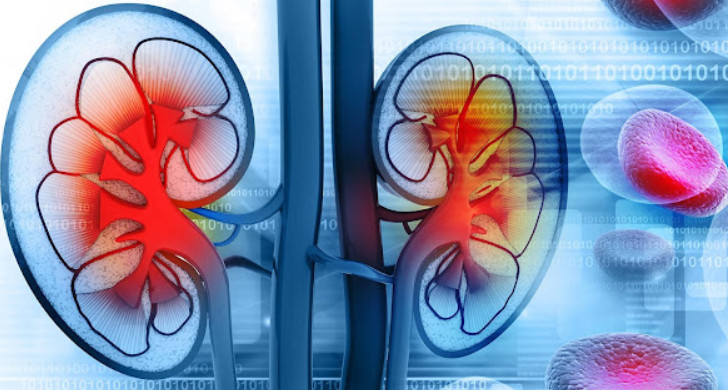

Bubrezi su vitalni organi u ljudskom tijelu koji igraju ključnu ulogu u održavanju ravnoteže unutar organizma. Filtriraju krv, eliminiraju otpadne tvari, reguliraju ravnotežu tekućina, minerala i elektrolita, te održavaju krvni pritisak. Zbog svoje kompleksne funkcije, bubrezi su esencijalni za pravilno funkcionisanje organizma. Nažalost, mnogi ljudi nisu svjesni problema s bubrezima dok ne dođe do značajnog oštećenja, zbog čega je prepoznavanje ranih simptoma od suštinske važnosti. Pravovremena dijagnoza može spriječiti ozbiljne komplikacije.

Hronični umor i slabost često se zanemaruju, ali mogu biti ozbiljan znak problema s bubrezima. Bubrezi proizvode hormon eritropoetin, koji stimulira proizvodnju crvenih krvnih zrnaca. Kada bubrezi ne rade ispravno, nivo ovog hormona opada, što može dovesti do anemije. Osobe koje se osjećaju iscrpljeno bez očiglednog razloga trebaju potražiti medicinsku pomoć. Takođe, oticanje dijelova tijela, poput nogu, zglobova i lica, može ukazivati na zadržavanje tekućine, stanje poznato kao edem.

Poremećaji u ravnoteži elektrolita, poput kalcija, kalija i magnezija, mogu dovesti do mišićnih grčeva i sindroma nemirnih nogu. Ovi simptomi mogu značajno utjecati na kvalitet sna i svakodnevne aktivnosti, pa je preporučljivo posjetiti ljekara radi dijagnostike i odgovarajućeg tretmana.

Ako primijetite bilo koji od ovih simptoma, obavezno se obratite svom ljekaru. Ljekar može preporučiti razne testove, uključujući laboratorijske analize krvi i urina, ultrazvuk bubrega ili druge dijagnostičke procedure. Rano prepoznavanje i dijagnoza ključni su za prevenciju ozbiljnih komplikacija koje mogu nastati uslijed bubrežnih bolesti.